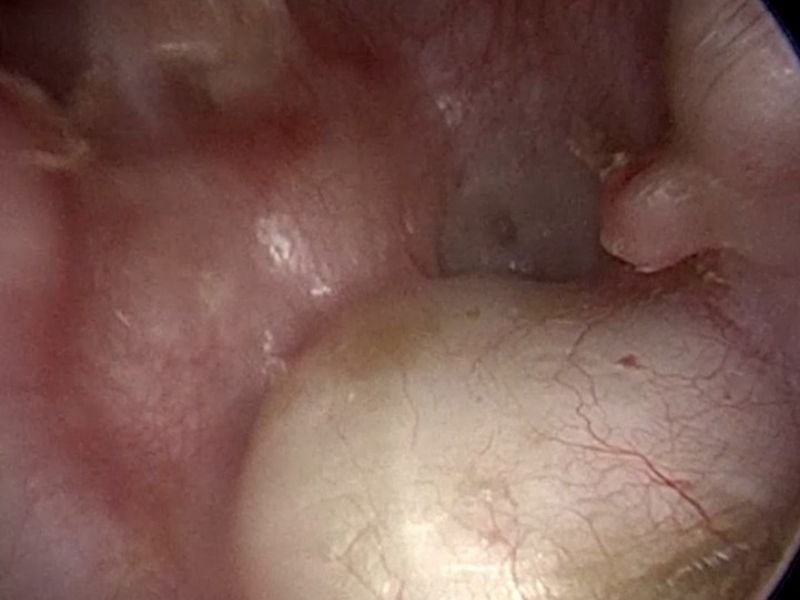

O que é o tímpano e por que ele pode ser danificado?

O tímpano é uma membrana fina localizada no ouvido médio, responsável por converter ondas sonoras em vibrações que são interpretadas pelo cérebro. Ele pode ser danificado por:

Quando o tímpano é perfurado, a capacidade auditiva é significativamente reduzida, o que pode impactar a vida social, profissional e emocional do paciente.